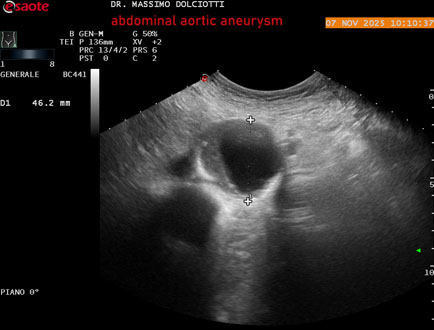

Data inserimento: 11/11/2025

Ecografia del: 07/11/2025

Strumento: Esaote MyLab Eight

Sonda: Convex Multifrequenza 1-8 MHz

Età Paziente: M 60 anni

Motivazione dell'esame: follow up per aneurisma dell'aorta addominale.

Commento all'esame: le immagini ed il video documentano la presenza dell'aneurisma dell'aorta addominale sotto-renale, con diametro antero-posteriore massimo documentato di 47 / 48 mm.

Conclusioni: aneurisma dell'aorta addominale in follow up (abdominal aortic aneurysm follow-up).

Presentazione: Dr. Massimo Dolciotti - Ancona